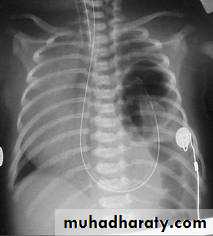

Diagnosis:-- CXRo Air & fluid filled loops of bowel in the chest.o Paucity of intestinal gas in the abdomen.o Mediastinal shift (heart shifted to the right).o Tip of NG tube seen in the chest.

-- Barium study

Treatment: ➣Resuscitation NG tube Bag mask ventilation is contraindicated Endotracheal intubation + oxygen. Urinary catheter Arterial & venous line Fluid therapy Echo study Refer to pediatric surgical center